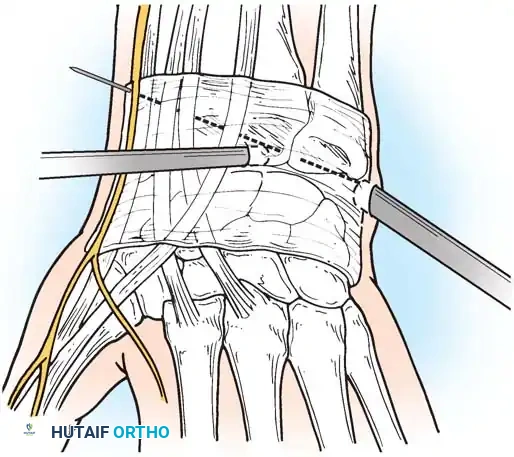

In cases of severe instability or concomitant ECU subsheath disruption, open capsular repair and ECU stabilization are required.

Open repair of the dorsal capsule and TFCC, ensuring robust closure and stabilization of the ulnar-sided structures.

Stabilization of the ECU tendon and subsheath, a critical step in addressing complex ulnar-sided wrist trauma.

If the DRUJ remains unstable after soft tissue repair, temporary transarticular K-wire fixation may be necessary to protect the repair during the initial healing phase.

Radiographic confirmation of temporary transarticular K-wire fixation stabilizing the DRUJ following complex TFCC repair.